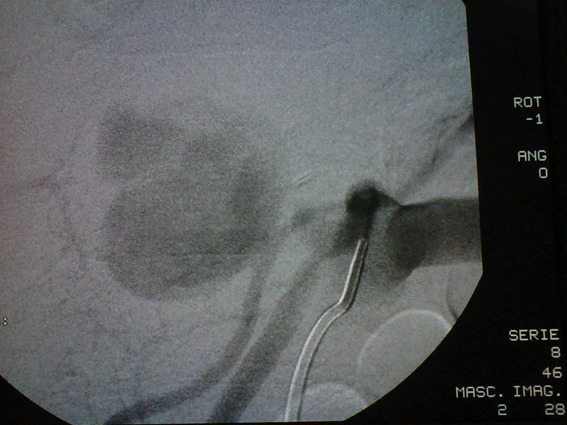

A 69-year-old man underwent liver transplantation with a deceased donor for cirrhosis secondary to steatohepatitis. The arterial anastomosis was performed between the celiac trunk of the donor and the hepatic artery of the recipient. In the second postoperative month, he developed abdominal pain and abnormal liver function tests. MRI angiography and subsequent digital angiography confirmed a 50 x 60 mm hepatic artery pseudoaneurysm (PAH) with dilation of the bile duct and bilomas in both hepatic lobes. Endovascular treatment could not be performed due to the absence of contrast passage to the intrahepatic branches during angiography. A surgical ligation and resection of the PAH that compromised both hepatic arteries was chosen. The primary anastomosis was not viable because it was not possible to identify a viable proximal end or ostium. Given the ischemic compromise of the bile duct, an exception route for re-transplantation was requested from INCUCAI, thus entering the waiting list and accessing a new graft 30 days later. His subsequent evolution was favorable. Now he's asymptomatic under follow-up after 9 years of the liver re-transplantation.